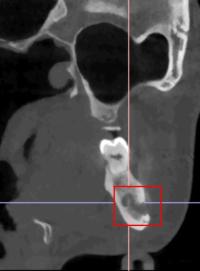

医生检查发现,王女士右侧下颌体部区域有明显包块,周围皮肤发红、肿胀,按压时有疼痛感。口腔内检查显示她存在多颗龋坏牙齿和残根,其中几颗叩击痛明显。拍摄的X光片进一步揭示了问题所在:她的下颌骨深处有一片不规则的“阴影区”,而且这个病灶离下颌骨里重要的神经血管非常近,若再拖延,可能会损伤神经,甚至导致面部变形。

结合临床表现和影像学检查,医生诊断王女士患有“下颌骨骨髓炎”—— 这是一种颌骨被细菌感染引发的炎症,就像骨骼被 “虫蛀” 一样,若不及时清除感染,炎症会持续破坏骨组织。病房医疗团队立即制定了综合治疗方案:首先进行抗感染治疗,控制炎症发展;随后进行手术清创,彻底刮除受感染的死骨组织。“考虑到王女士对外观的顾虑,我们特意选择从口内做切口,避免术后脸上留疤。”口腔颌面外科病房主任孙超解释说。